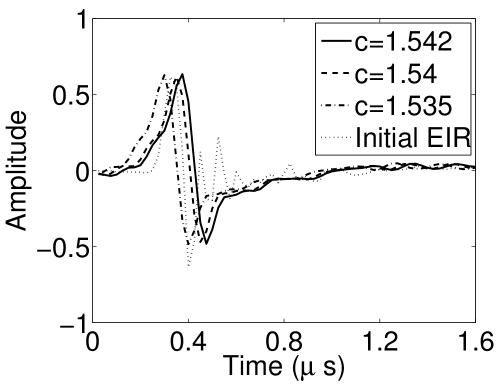

VI-F Auto-focus capabilities

Conventional PACT reconstruction algorithms assume that the medium is described by a constant speed-of-sound (SOS) value. In practice, this value may not be known precisely and can be tuned [TVZL2011] to maximize the spatial resolution of the reconstructed images. The effect of an incorrect SOS value can sometimes be compensated for by use of the VP algorithm due to modification of the EIR during the joint estimation. Figures 19(a) and 19(b) show images reconstructed by use of the conventional iterative method and the VP algorithm, respectively, when different constant SOS values are assumed. The 2D imaging model that ignored the SIR was employed. Nearly identical images were reconstructed by use of the VP algorithm, even though the assumed SOS values were different in each case. The images contained reduced artifact levels as compared to those reconstructed by use of the conventional method. The recovered EIRs differed by a time shift (as displayed in Fig. 19(c)). Since the object was located near the center of the transducer array and was small compared to the radius of the array, the scaling effect due to the inaccurate SOS can be approximated by the shift of the EIR, which explains how the recovered EIR compensates for the error in SOS value.